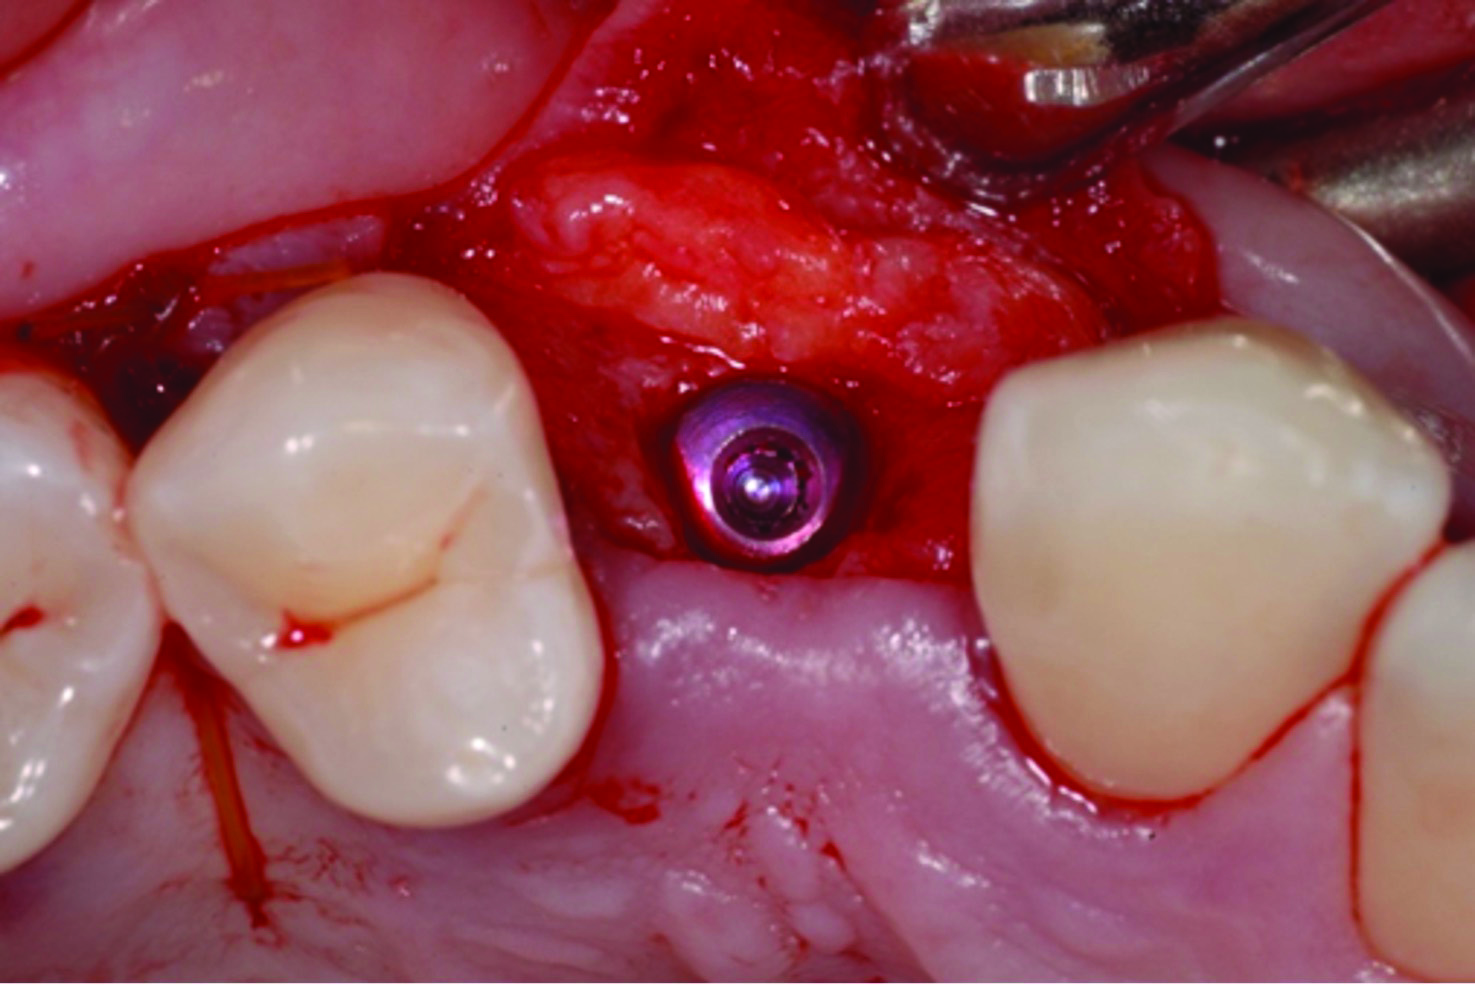

Fig 12 through Fig 14. Example of increasing MT with a roll technique. Fig 12: incision design for implant placement with a healing abutment placement and to enhance MT; the recipient site is prepared on the buccal side; the palatal aspect of the flap will be rolled to the buccal recipient site; Fig 13: insertion of roll of tissue taken from the palatal aspect of the flap; Fig 14: implant placement with healing abutment.